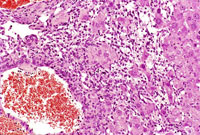

This hemangiosarcoma is poorly demarcated from surrounding parenchyma and consists of dilated blood-filled spaces and sheets of proliferating endothelial cells.